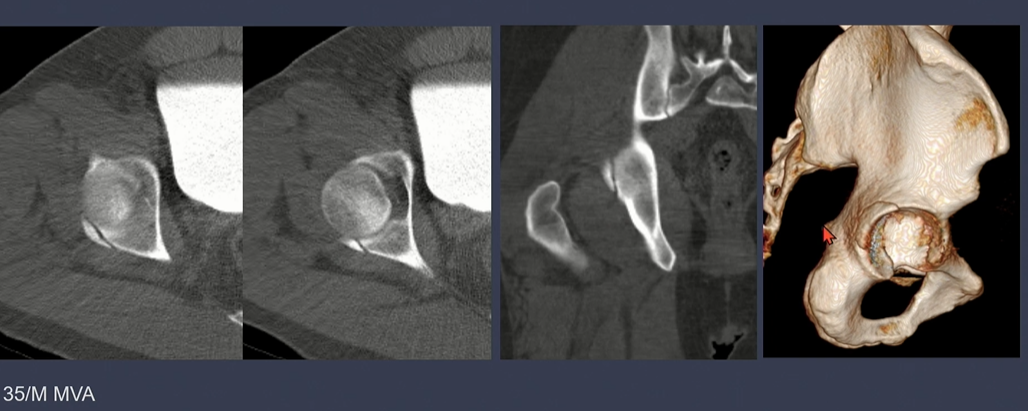

displacement가 없는 경우.

displacement가 있는 경우

CT상 골절선 확인. 가장 좌측 iliac wing, 중간 사진은 Quadrilateral plate에 골절선이 있음.